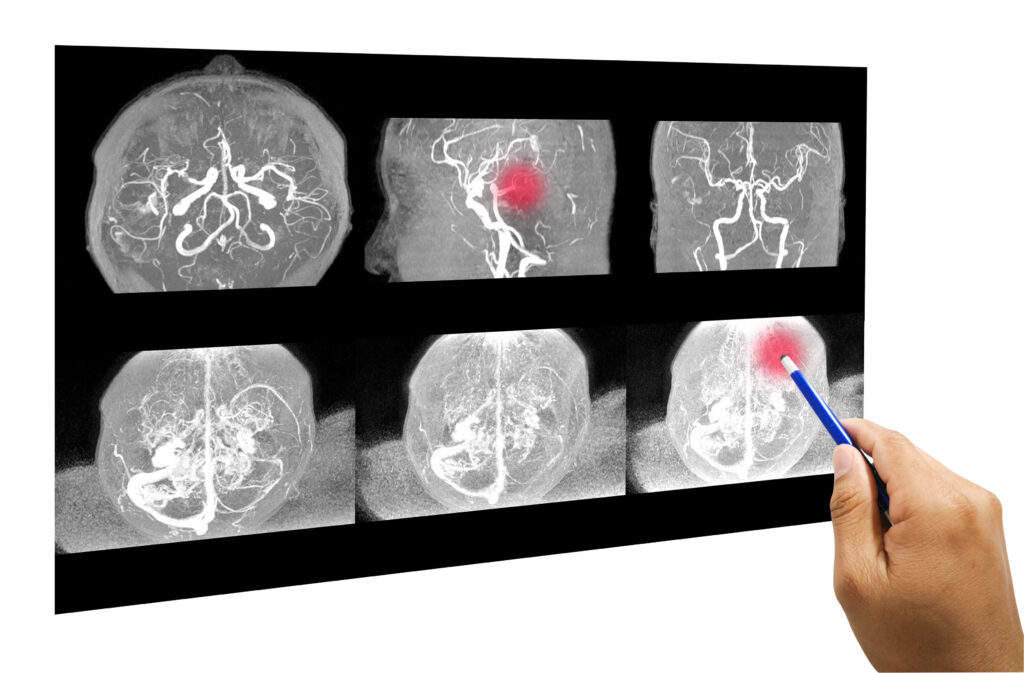

Atacul cerebral sau accidentul vascular cerebral (AVC) reprezintă ruperea sau blocarea  vaselor de sânge ce ajung la creier, astfel că o parte a encefalului ajunge să nu mai beneficieze de suficient sânge și oxigen.